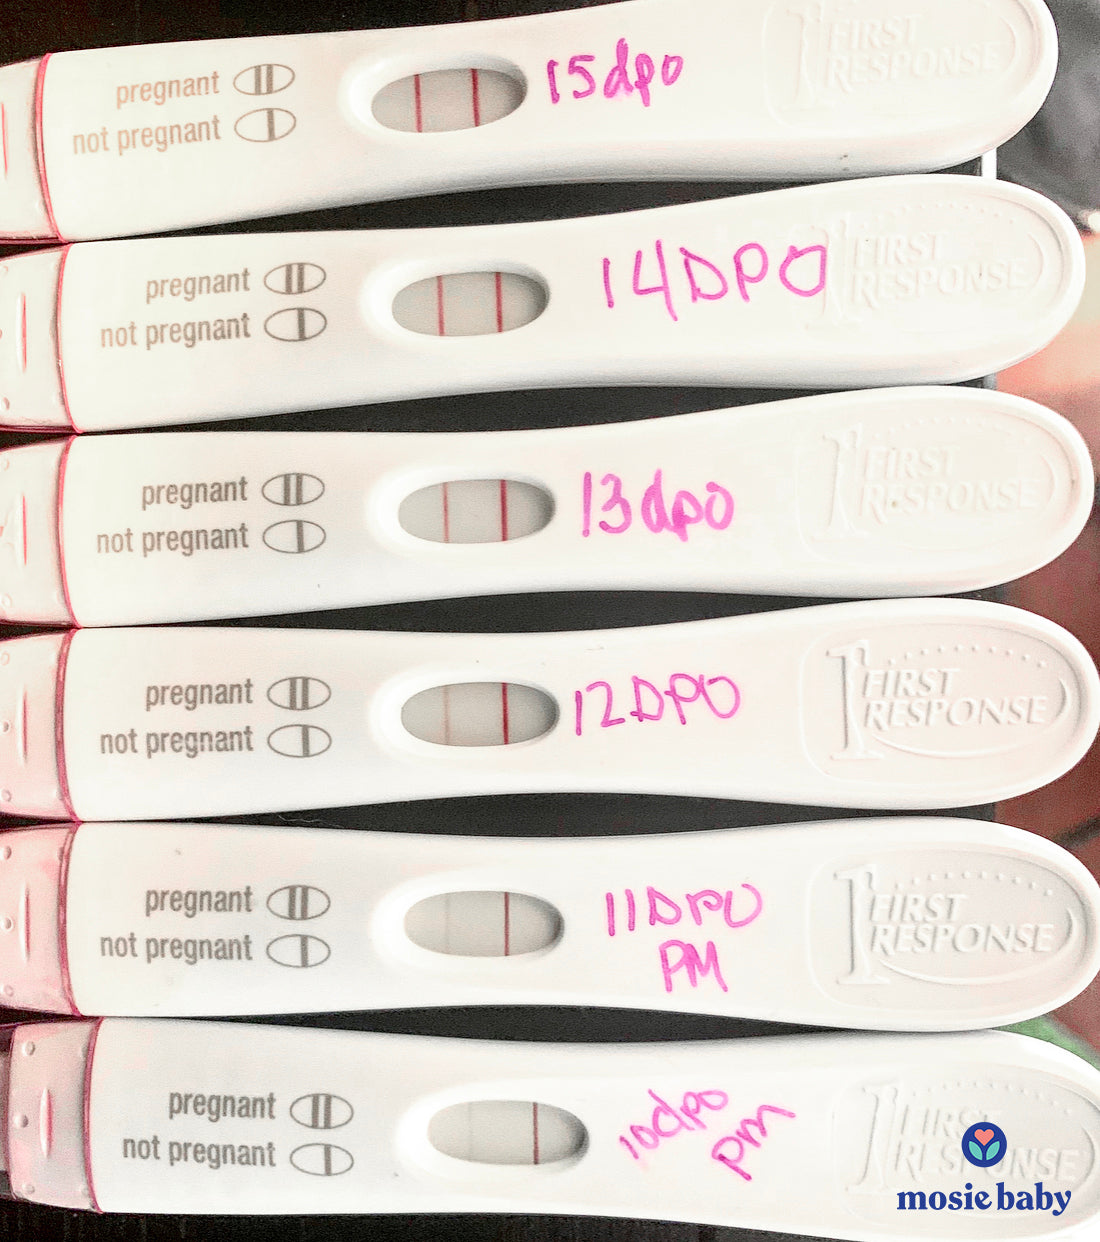

10 Failures with a Regular Syringe Led Them To A Mosie Success!